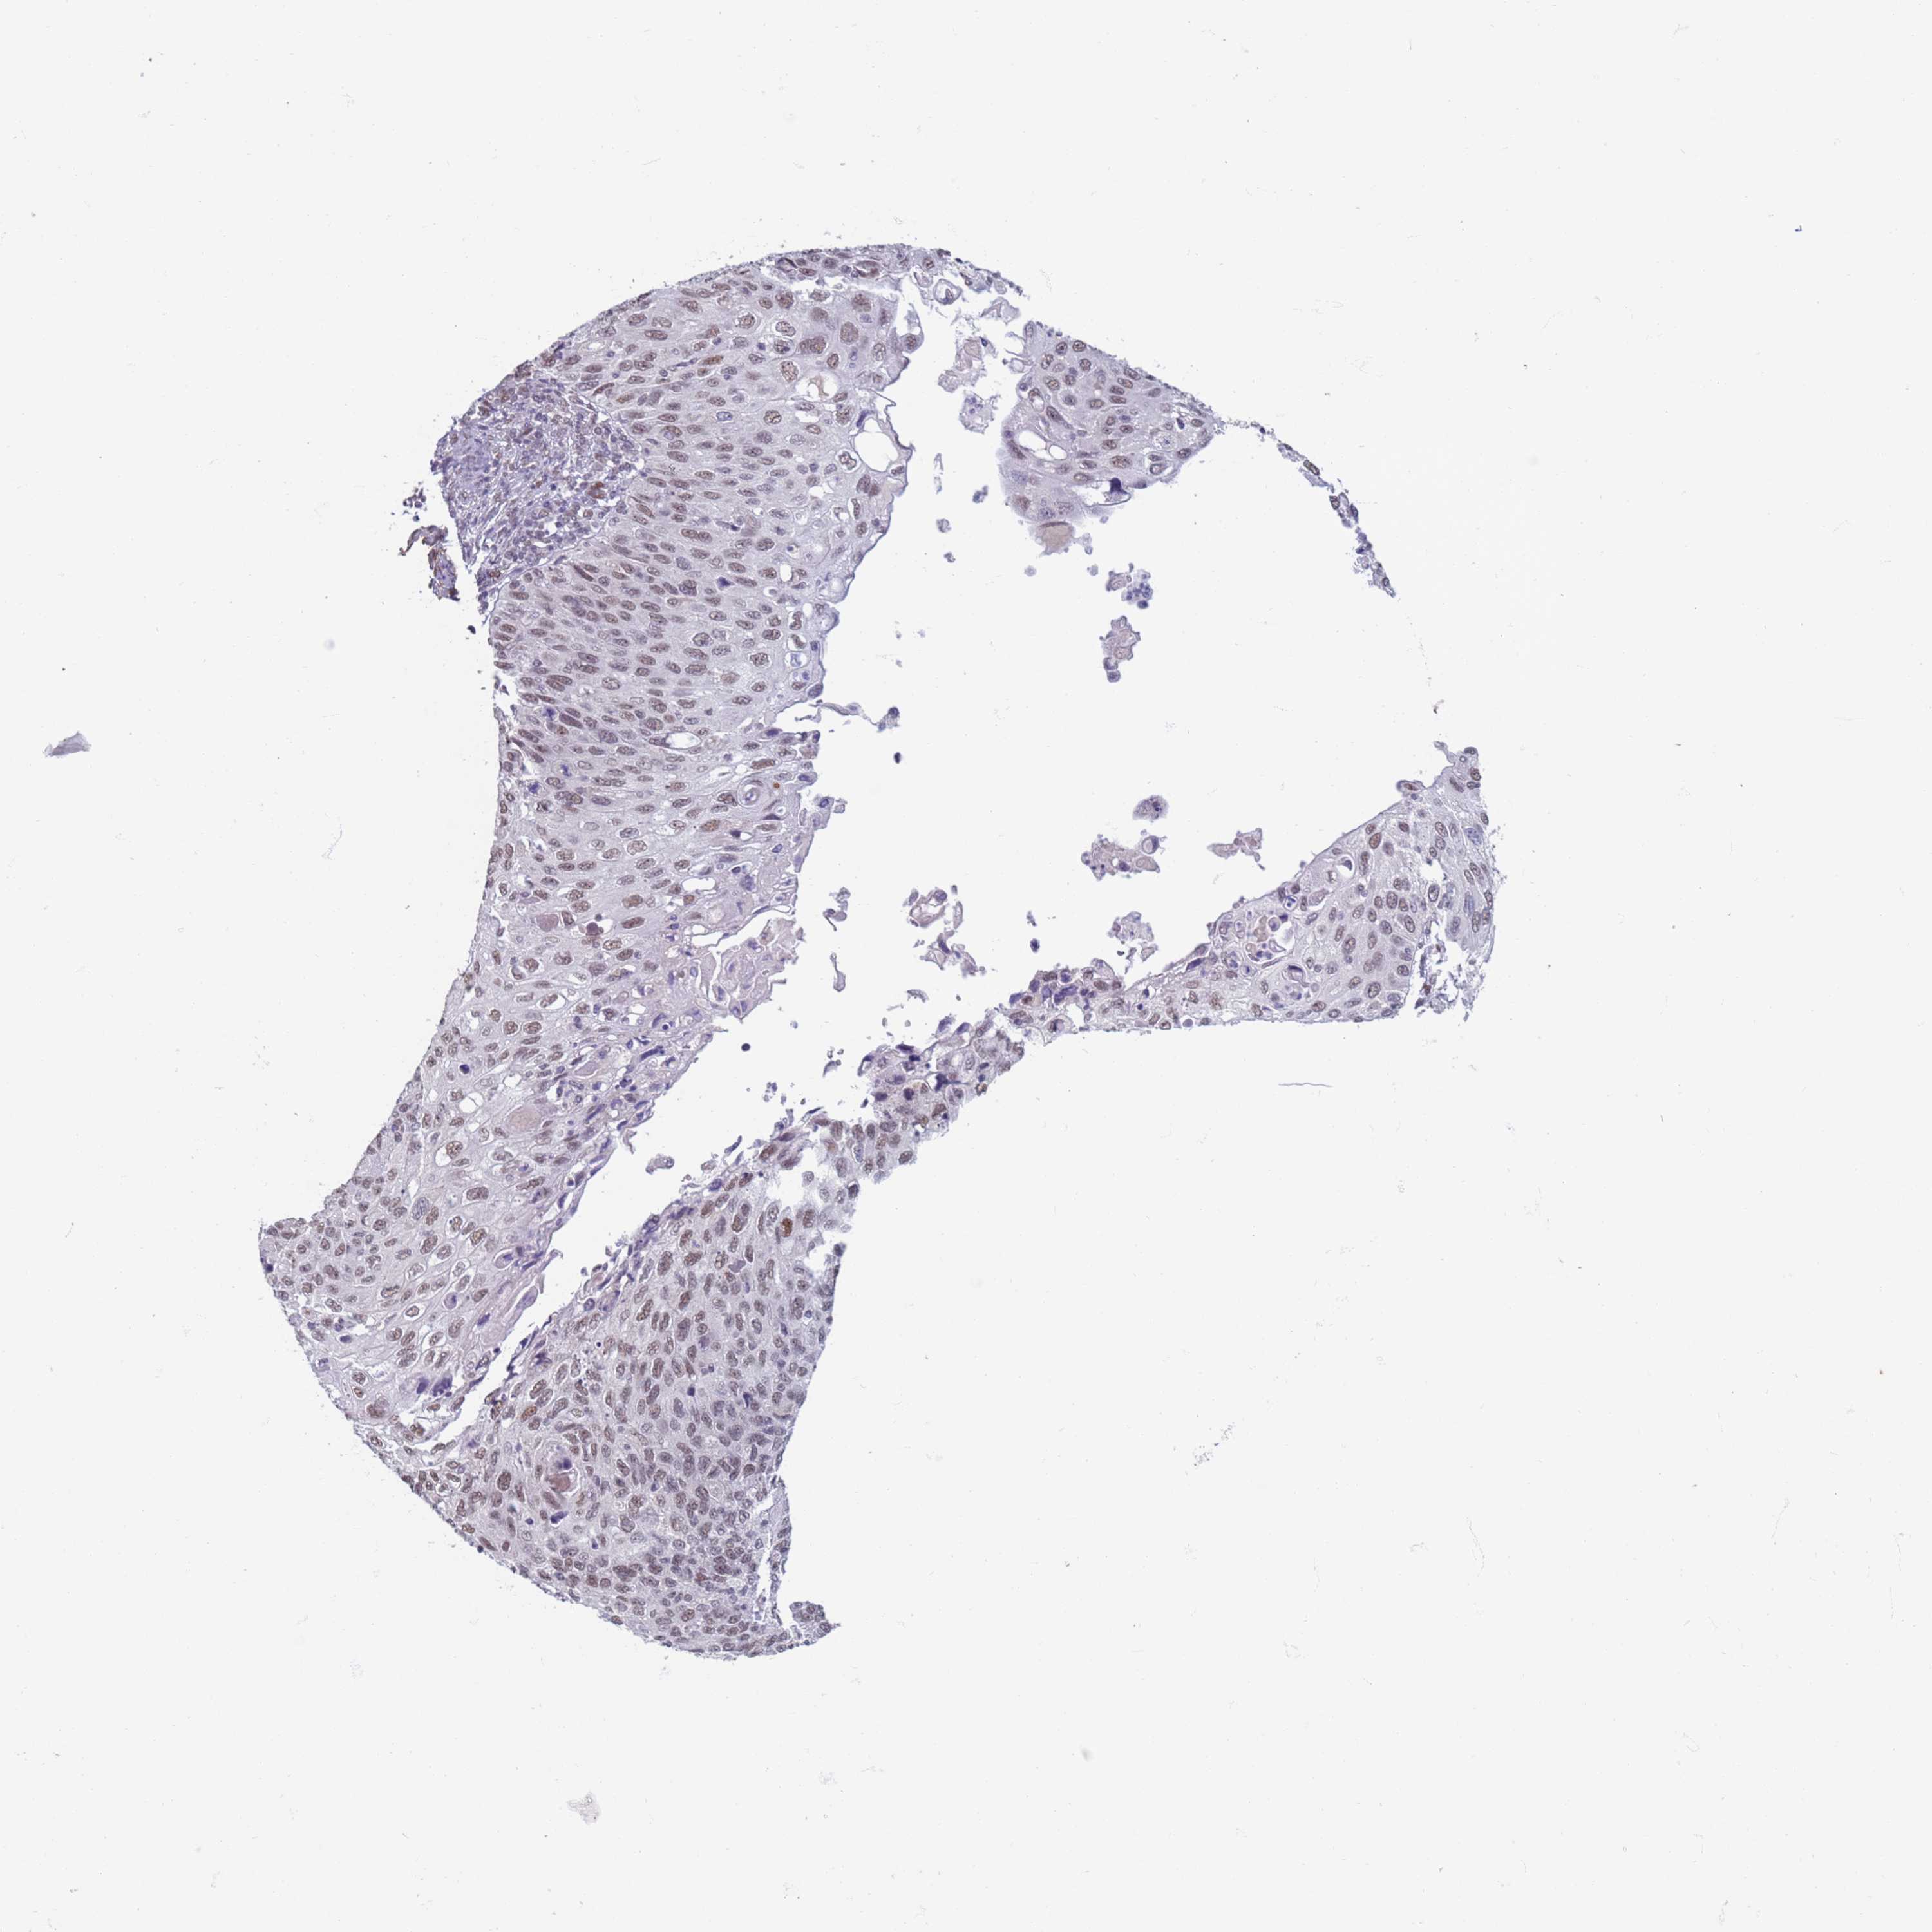

CERVICAL CANCER - Protein expressioni

A mouse-over function shows sample information and annotation data. Click on an image to view it in a full screen mode. Samples can be filtered based on level of antibody staining by selecting one or several of the following categories: high, medium, low and not detected. The assay and annotation is described here.

Note that samples used for immunohistochemistry by the Human Protein Atlas do not correspond to samples in the TCGA dataset.

Antibody stainingi

Antibody staining in the annotated cell types in the current human tissue is reported as not detected, low, medium, or high, based on conventional immunohistochemistry profiling in selected tissues. This score is based on the combination of the staining intensity and fraction of stained cells.

Each image is clickable and will lead to virtual microscopy that enables deeper exploration of all samples and also displays staining intensity scores, fraction scores and subcellular localization as well as patient and tissue information for each sample.

Antibody HPA041906

Antibody HPA043552

Staining

High

Medium

Low

Not detected

Intensity

Strong

Moderate

Weak

Negative

Quantity

>75%

75%-25%

<25%

None

Location

Nuclear

Cytoplasmic/membranous

Cytoplasmic/membranous,nuclear

Squamous cell carcinoma, NOS

Adenocarcinoma, NOS